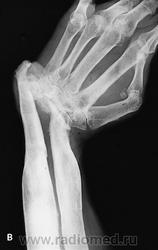

Сочетанная дисплазия: диафизарная+остеохондродисплазия. Нужны другие кости, череп, позвоночник, клинические данные о росте и видимых уродствах, иначе это просто угадайка (во всяком случае для меня)...

Деформация Маделунга?

Какая-то дисхондроплазия, м.б. разновидность болезни Олье? Хотя смотрел последнюю подборку не совсем похоже. Дисхондроплазия.